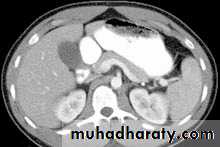

Enhanced + Unenhanced CT

Hepatoma + met.

Met. adenocarcinoma